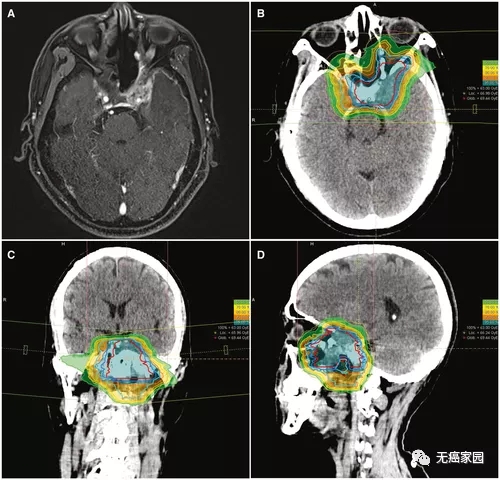

典型的碳离子放射治疗 (CIRT) 治疗计划,包含 3 个视野。该患者患有局部晚期、局部复发性鼻咽癌(T4N0M0 疾病),接受了 63 gray的碳离子放射治疗,分 21 次。

图示高辐射剂量集中于肿瘤部位,周边正常组织无/极少剂量

图注:图中强度调强质子治疗(IMPT)的辐射主要集中于鼻咽癌病灶周围,对周围正常组织的无影响或影响较小,而强度调强放射治疗(IMRT)的辐射面积较大,涵盖病灶及周围正常组织